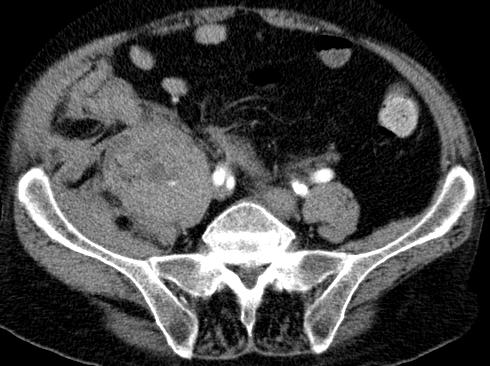

egyidejű kis obturator externus haematoma